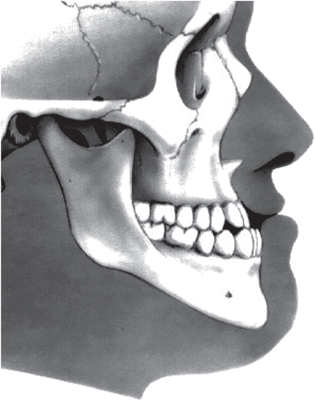

Unwanted dentoalveolar changes occur with tooth-borne appliances. For example, an expander used to correct crossbite in a patient with skeletal hyperdivergence may worsen the divergence and lead to an anterior open bite, aggravate profile convexity, and trigger an unfavorable counter-clockwise rotation of the mandible [11]. Growth processes can transform a Class III patient into an apparent Class I (i.e. normal) through clockwise rotation of the mandible (see figure 1). If the space–time linearity of orthodontic events or linearity of therapeutic responses cannot be relied upon, how do orthodontists establish a reasonable basis on which to assess the efficiency/efficacy of their interventions?

Figure 1. Class III malocclusion: protrusion of the lower dental arch. A malocclusion is a misalignment or incorrect relation between the teeth of the two dental arches when they approach each other as the jaws close.

A considerable difference exists between the number of variables (recognized as being no more than seven) that the human brain can handle simultaneously for making decisions, and the amount of clinical, functional, anamnestic, and radiographic data available for each orthodontic patient [16]. To understand each clinical case better, the practising orthodontist must follow a rather meandering diagnostic path. Averages are not suitable for describing phenomena in which reciprocal interactions are at work. Finally, the amount and quality of clinical and/or anamnestic information, as well as the problematic conceptual assumption of 'harmony' and 'balance' related to floating and overlapping phenotypic contours of the Class III dentoskeletal imbalance (figure 1) are important [17–19].